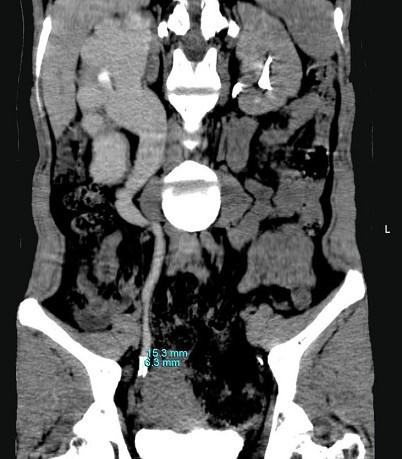

问题 女,42岁,反复右下腹部绞痛向会阴部放射1 月,CT检查如图示,下列诊断正确的是 ( )

选项 A、右侧输尿管下段结核,其上方输尿管扩张积水 B、右侧输尿管下段炎性狭窄,其上方输尿管扩张积水 C、右侧输尿管中段结石,其上方输尿管扩张积水 D、右侧输尿管下段结石,其上方输尿管扩张积水 E、右侧输尿管上段结石,其上方输尿管扩张积水

答案 C